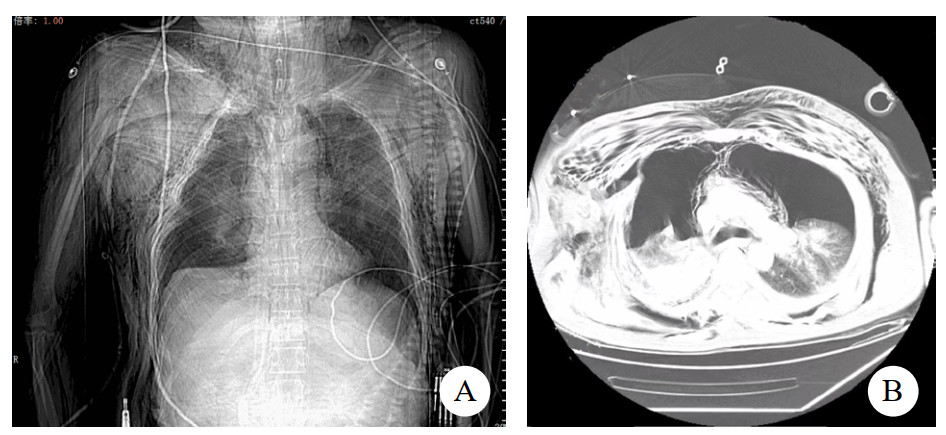

入院查体:患者意识清,烦躁不安,体温36.2℃,心率112次/min,呼吸38次/min,血压107/72 mmHg(1 mmHg=0.133 kPa),SPO2 92%,颈部肿胀淤血;颈部、胸部、腹壁下多发捻发感;双肺叩诊呈鼓音;听诊双肺呼吸音消失。辅助检查:血气分析:氧分压(PO2)51.3 mmHg,二氧化碳分压(PCO2)67.2 mmHg,碱剩余(BE)-8.4 mmol/L,pH 7.15,乳酸4.5。血常规:HGB 104 g/L。头颅+胸部CT:脑沟、脑裂及脑室多发积气,主支气管塌陷,两侧支气管闭塞,两侧气胸伴部分肺组织膨胀不全,肺压缩70%,两侧多发肋骨骨折,两侧胸壁大量皮下气肿,右侧肩胛骨骨折,右侧锁骨骨折。床旁超声检查未见心肌收缩减弱,心包、胸腹腔未见明显积液(图 1)。初步诊断:主支气管断裂、双侧血气胸、肺挫伤,多发肋骨骨折,呼吸衰竭。就诊过程中患者出现意识不清,呼之不应,氧饱和进行性下降至65%,心率减慢至23次/min,监护仪提示室性逸搏心律,立即行心肺复苏、气管插管、双侧胸腔闭式引流、止血、补液等抢救,复苏10 min后患者恢复R0SC,结合检验检查考虑考虑主气管塌陷致急性呼吸衰竭而引起呼吸心搏骤停,急邀区域创伤中心多学科团队(multiple disciplinary team,MDT)远程会诊后建议行主气道修补术以改善患者通气维持机体氧供,但该院无手术条件需转上级医院,而经过积极对症治疗后患者病情无好转,呼吸机控制呼吸下(容量控制模式,潮气量8 mL/kg,呼吸频率42次/min,呼气末正压10 mmHg,氧浓度100%),氧合指数(PaO2/FiO2)持续下降至50 mmHg以下,血乳酸上升至8.2 mmol/L,达到(extracorporeal membrane oxygenation,ECMO)支持指征[1],急诊行体外膜肺氧合治疗,采用V-V ECMO(veno-venous ECMO)模式,选择右侧股静脉及右侧颈内静脉,右侧股静脉置入20Fr引血导管,右侧颈内静脉置入19Fr回血导管,使用迈柯唯公司ROTAFLOW离心泵及QUADROX PLS氧合器,设置参数:转速3500 r/min,血流量4 L/min,氧流量4 L/min,患者氧饱和度维持于90%左右。遂在呼吸机及ECMO支持下由救护车护送至本院EICU。

| A:CT检查示两侧多发肋骨骨折,两侧气胸;B:两侧胸壁大量皮下气肿伴部分肺组织膨胀不全 图 1 患者受伤入院当天CT影像 |